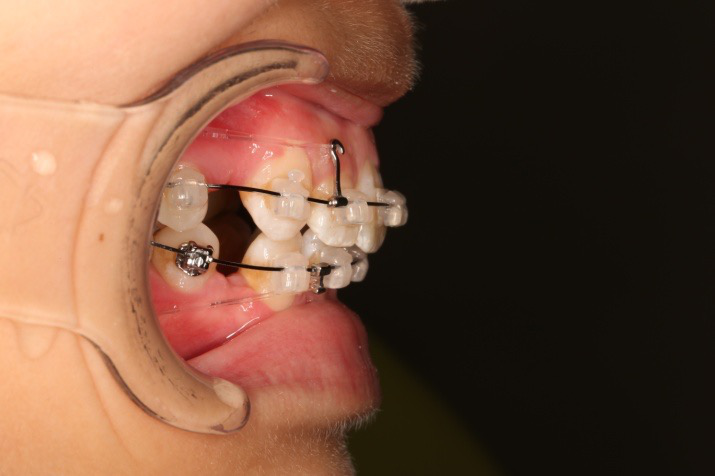

6.第9个月:2017.07.25 ◆ 上前牙加颈部弹力线

7.第13.5个月:2017.12.15 ◆ 36/46远中倾斜,改变下颌牵引位置

2017.07.25  上前牙加颈部弹力线

上颌使用高位种植钉及长牵引钩,配合尖牙近远中的v-bend,上颌前牙的牙齿移动方式是整体往上,往后内收。